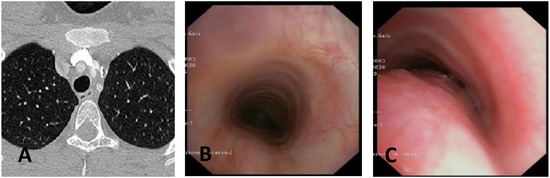

Diagnosis, Treatment, and Follow-Up of Tracheo/Bronchomalacia in Children: The Italian Multicenter Experience

by Angelo Florio, Michele Ghezzi, Francesca Rizzo, Paolo Del Greco, Katia Perri, Fabio Antonelli, Annalisa Gallizia, Francesco Santoro, Elena Ribera, Francesco Macchini, Michele Torre, Francesco Donati, Federica Lena, Vittorio Guerriero, Paola Borgia, Valerio Gentilino, Roberto D’Agostino, Federica Porcaro, Alessio Conte, Duino Meucci, Roberto Baggi, Michele Gaffuri, Pietro Salvati and Oliviero Saccoadd Show full author list remove Hide full author list

Children 2025, 12(11), 1511; https://doi.org/10.3390/children12111511 - 7 Nov 2025

Background: In pediatric age, the central airways are more flexible and mobile, with tracheal and bronchial walls easily tending to collapse, allowing partial or complete occlusion of the lumen: a situation described as tracheobronchomalacia (TBM). This is a condition that causes an increase [...] Read more.

Background: In pediatric age, the central airways are more flexible and mobile, with tracheal and bronchial walls easily tending to collapse, allowing partial or complete occlusion of the lumen: a situation described as tracheobronchomalacia (TBM). This is a condition that causes an increase in intrathoracic pressure that may accentuate airway collapse, and a biphasic or barking cough appears. Objectives: Although TBM is relatively frequent in pediatric age, the diagnostic criteria and subsequent treatment do not follow well-standardized criteria and often vary from pediatric center to center. Therefore, there is a need to standardize diagnostic procedures and the resulting medical or surgical treatments. Methods: We therefore organized a day of meetings to talk about TBM, inviting all Italian pediatricians and pediatric surgeons who diagnose and treat patients with this pathology on a daily basis. Results: This work, collecting all the meeting interventions, is a compendium that deals with all aspects of TBM, emphasizing the most correct criteria to diagnose and therefore best treat each pediatric patient with this clinical condition. We give particular emphasis to the need to perform static and dynamic videobronchoscopy (S/DVBS) to verify the patency of the tracheal lumen, so as to evaluate the severity of TBM. Conclusions: this work deals with TBM in all its diagnostic and treatment aspects and can be a valid help for all pediatricians who treat these patients. Full article

Show Figures

Figure 1